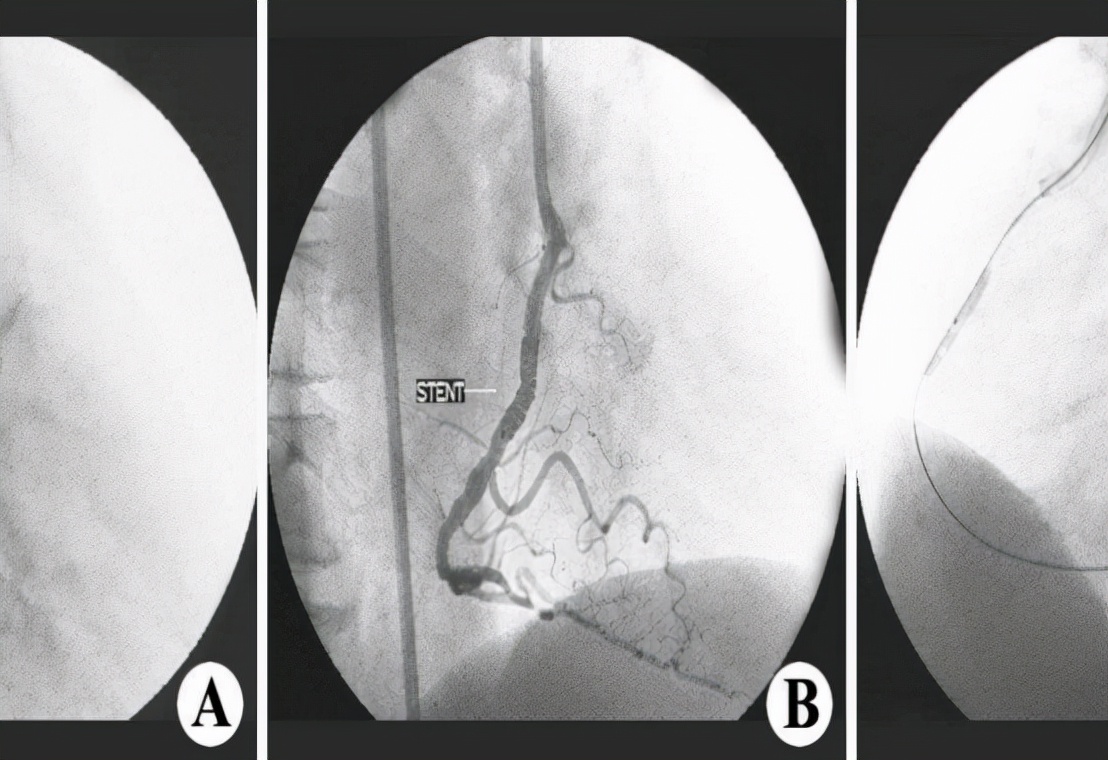

介入治疗是冠脉造影明确病变后,对严重狭窄区域进行球囊扩张,然后植入支架,使冠状动脉畅通,改善心肌缺血。它最大的优点是无需开胸,简单、安全、无痛。

冠状动脉CT成像(CTA)是一种无创、简单、快速的检查方法,是冠心病筛查和初诊的良好选择。冠脉造影(DSA)可以直观地了解冠状动脉狭窄的情况,是目前诊断冠状动脉疾病最可靠的方法,被誉为“金标准”。

冠脉造影是心脏的冠脉造影,是一种通过注射造影剂来检查心脏冠状动脉通透性的技术。当患者出现冠心病、心绞痛等症状时,应及时检查心血管系统的阻塞程度,以便后续介入或搭桥治疗。

冠脉造影是穿刺下肢股动脉或上肢桡动脉,然后用造影剂导管通过动脉通路到达冠状动脉开口处。然后,医生将造影剂注入冠状动脉,通过X光记录冠状动脉的发展,并根据成像结果判断冠状动脉是否病变、变形和痉挛。

冠脉造影本身是一种侵入性检查,需要住院,进入导管实验室,在X线下完成,整个过程与放置心脏支架的过程几乎相同。所有的冠脉造影本身也可以认为是一种接近手术的检查,而且是一种微创手术。